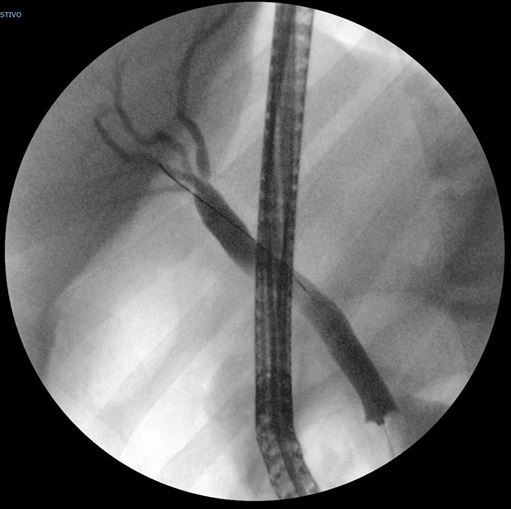

Se ingresa en planta a cargo de Digestivo Infantil, donde se pauta analgesia intravenosa, con la que se consigue buen control del dolor. Al no ser posible localizar el cálculo con la ecografía, se solicita colangiorresonancia, donde se aprecia un cálculo impactado en la papila, con marcada dilatación del colédoco y colelitiasis múltiples. Tras confirmar la existencia de coledocolitiasis, se realiza colangiopancreatografía retrógrada endoscópica (CPRE). Durante la CPRE se aprecian hallazgos sugestivos de litiasis expulsada recientemente; se realiza esfinterotomía y se extrae barro biliar (Fig. 2). La evolución posterior fue favorable, sin complicaciones tras el procedimiento. Además, se programa colecistectomía, que se realiza sin incidencias.

| Figura 2. Colangiopancreatografía retrógrada endoscópica (CPRE) en la que se aprecia dilatación de la vía biliar extrahepática, con vía intrahepática normal. No se aprecian defectos de repleción intraluminales |